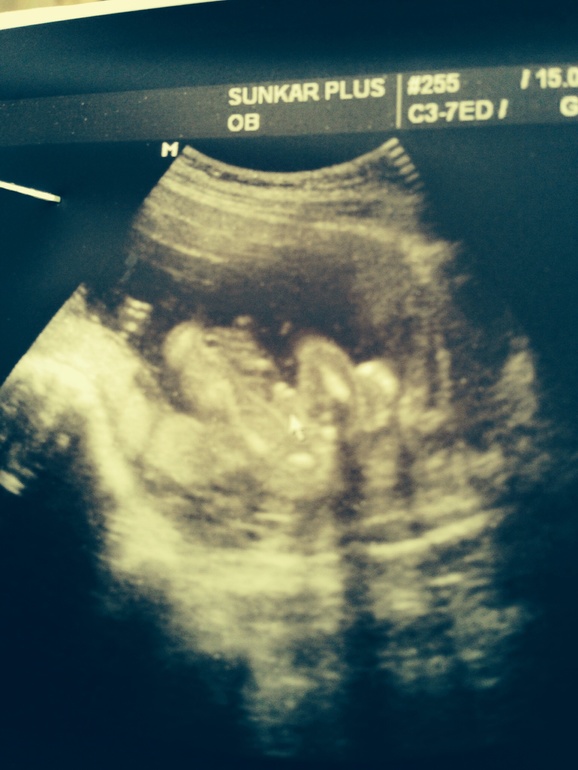

Вопросы про УЗИ, обследования и анализы: что, где, как, когда?Пошла на узи в платную клинику с хорошей аппаратурой и как мне кажется хорошими специалистами. Срок был 17 недель и 3 дня ( где то так). С главной целью узнать пол. Мне сказали мальчик. Я обрадовалась , но когда показала фото родным , говорят какое то маленькое у него хозяйство, обычно по более бывает. Вот теперь я не знаю что думать , ребенок первый , еще до узи не знаю почему чувствовала что это мальчик. Что скажете?на кого похоже?

Врач же не только с этого ракурса посмотрела, просто фото сделала как получилось. Конечно маленькое хозяйство видно, оно же за яйками ещё, по моему очевидно, что мальчик, даже не специалисту )

хозяйство как хозяйство,два узи мальчика видела,у вас похоже что сыночек!Здоровья вам и малышу